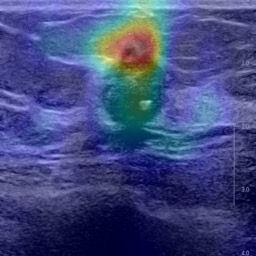

Ultrasonography is an important routine examination for breast cancer diagnosis, due to its non-invasive, radiation-free and low-cost properties. However, it is still not the first-line screening test for breast cancer due to its inherent limitations. It would be a tremendous success if we can precisely diagnose breast cancer by breast ultrasound images (BUS). Many learning-based computer-aided diagnostic methods have been proposed to achieve breast cancer diagnosis/lesion classification. However, most of them require a pre-define ROI and then classify the lesion inside the ROI. Conventional classification backbones, such as VGG16 and ResNet50, can achieve promising classification results with no ROI requirement. But these models lack interpretability, thus restricting their use in clinical practice. In this study, we propose a novel ROI-free model for breast cancer diagnosis in ultrasound images with interpretable feature representations. We leverage the anatomical prior knowledge that malignant and benign tumors have different spatial relationships between different tissue layers, and propose a HoVer-Transformer to formulate this prior knowledge. The proposed HoVer-Trans block extracts the inter- and intra-layer spatial information horizontally and vertically. We conduct and release an open dataset GDPH&GYFYY for breast cancer diagnosis in BUS. The proposed model is evaluated in three datasets by comparing with four CNN-based models and two vision transformer models via a five-fold cross validation. It achieves state-of-the-art classification performance with the best model interpretability.

翻译:超声波分析是乳腺癌诊断的一个重要常规检查,原因是其非侵入性、无辐射和低成本的特性。然而,由于其内在局限性,它仍不是乳腺癌的第一线筛选测试。如果我们能够精确地通过乳房超声图像诊断乳腺癌(BUS),它将是一个巨大的成功。我们提出了许多基于学习的计算机辅助诊断方法,以实现乳腺癌诊断/感官分类。然而,其中多数方法需要事先确定性能模型,然后对ROI内部的跨值进行分类。常规分类支柱,如VGG16和ResNet50等,可以在没有ROI要求的情况下实现有希望的分类结果。但是这些模型缺乏可解释性,从而限制了其在临床实践中的使用。在本研究中,我们提出了一个新的无乳腺癌诊断模型,在超声波图像中进行解释性特征描述。我们利用了先前的解剖学学学知识,即恶性肿瘤和良性肿瘤模型在不同组织层之间有着不同的空间关系,并提议采用状态解析法来编制这一先前的知识。拟议中的HOVer-Trans-Trading-Tradef-trainal Ex-deal-dealal-deal-deal-deal-degraphal-deal-deal-deal-deal-deal-deal disal disal-dal-dal-dal-dal-dal-deal-deal-dal-deal-deal-deal-dal-dal-dal-dal-dal-dal-dal-dal-dal-dal-dal-dal-dal-dal-I-dal-Iversal-dal-Ial-d-d-I-d-d-I-I-I-I-I-I-I-I-I-I-I-I-I-I-I-I-I-I-I-I-I-I-I-I-I-Ial-I-Ial-Ial-I-I-I-I-I-I-I-I-I-I-I-I-I-I-I-I-I-I-I-I-I-I-I-I-I-I-I-I-I-I-I-I-